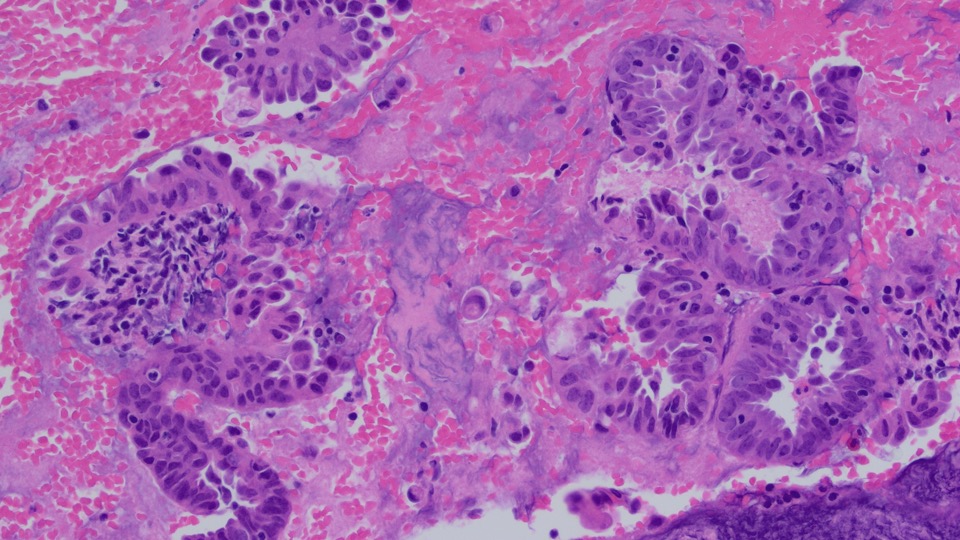

A 45-year old man with a history of PTC, tall cell variant (PT3b N1a M0), s/p total thyroidectomy, central neck lymph node excision and radioactive iodine therapy, presents with new neck mass. Figures a & b show FNA of the mass.